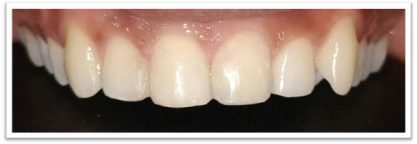

Patient Name: Rakesh Sinha

Tooth Involved : 11 12 21

Diagnosis : Caries Involving Enamel And Dentin Mesiocclusally

Treatment : Direct Composite Restorations Using Nanohybrid Composite

Before

After